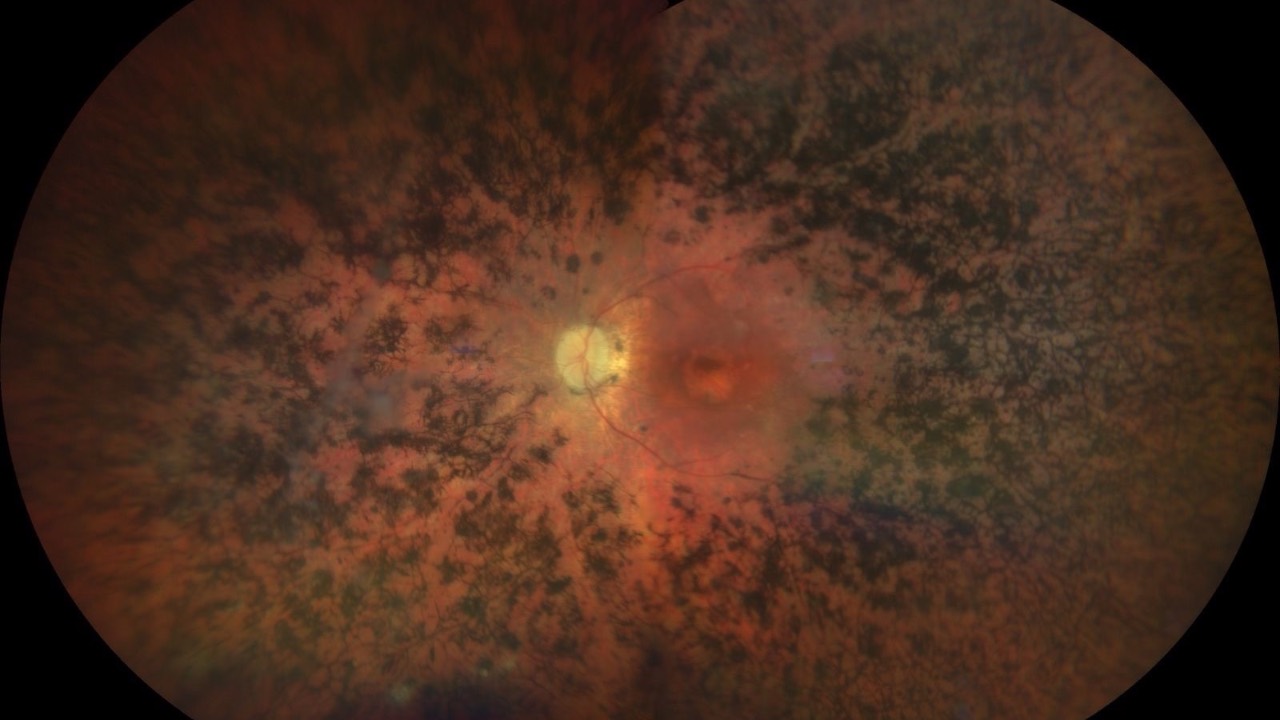

Photobiomodulation for Retinitis Pigmentosa

Do you know the how & why?

There has been promising results utilizing photobiomodulation as a potential treatment for retinitis pigmentosa (RP), as well as other retinal conditions such as macular degeneration (AMD), Stargardt's, and diabetic retinopathy. Recent findings utilizing multiwavelength...